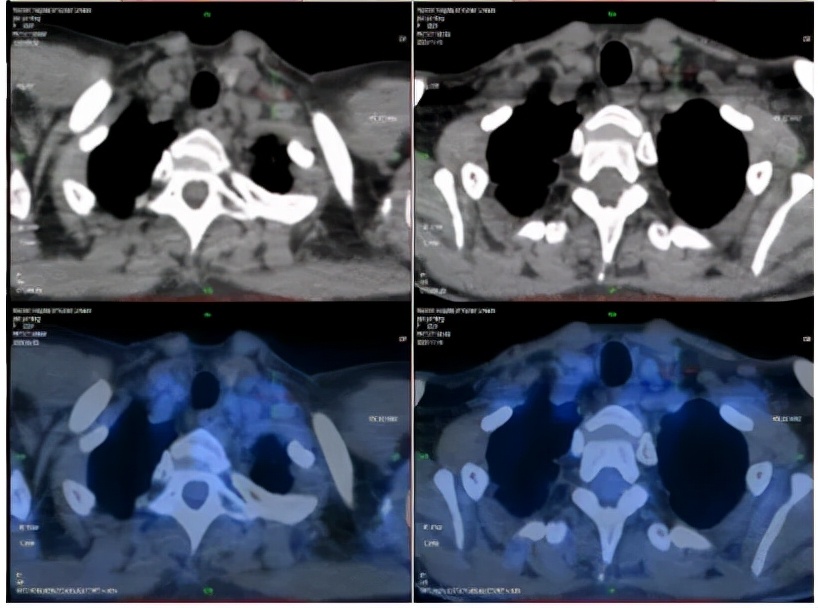

2020-4-22PET-CT提示:1. 胰腺体尾部稍低密度团块;肝内见多发团块、结节灶;肝门区、胰腺周围、腹膜后区多发肿大淋巴结;全身多发骨质密度不均;上述病灶代谢增高,考虑恶性病变,胰腺癌伴全身多发转移;2. 左锁骨上区及胸廓入口处淋巴结,代谢稍增高;不除外转移可能。

PET-CT(2020-04-22)